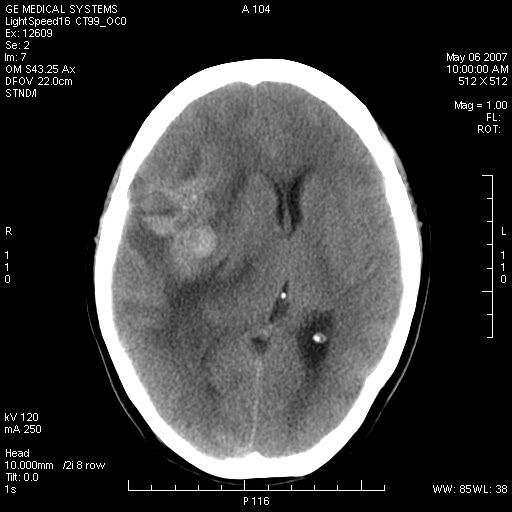

女,60岁,头痛6~7天。

右颞叶巨大高低混杂密度肿块,病灶内可见多发条块状钙化影,占位效应明显,中线结构显著左偏,肿块周围水肿明显,临近颅骨吸收变薄,边缘光整,考虑1少枝胶质瘤2脑膜瘤3转移瘤4室管膜瘤5淋巴瘤6三叉神经瘤(多多益善)合并镰下疝

右颞叶分叶状稍高密度灶,占位效应明显,外周见水肿带,其内见点条样高密度钙化灶,临近颅骨变薄,考虑:脑膜瘤,少突胶质瘤。

右颞叶混杂密度,累及右额叶。其内可见条片状钙化及斑片状略高密度,周围少量水肿,右颞骨吸收变薄,中线结构左移。考虑1少突胶质瘤。2脑膜瘤。合并瘤卒中。建议增强扫描。

右额、颞叶巨大高低混杂密度肿块,病灶内可见多发条块状钙化影,占位效应明显,中线结构显著左偏,肿块周围水肿明显,临近颅骨吸收变薄,边缘光整。

考虑:1、少枝胶质瘤;

2、脑膜瘤?

3、镰下疝;

4、建议增强扫描进一步检查。